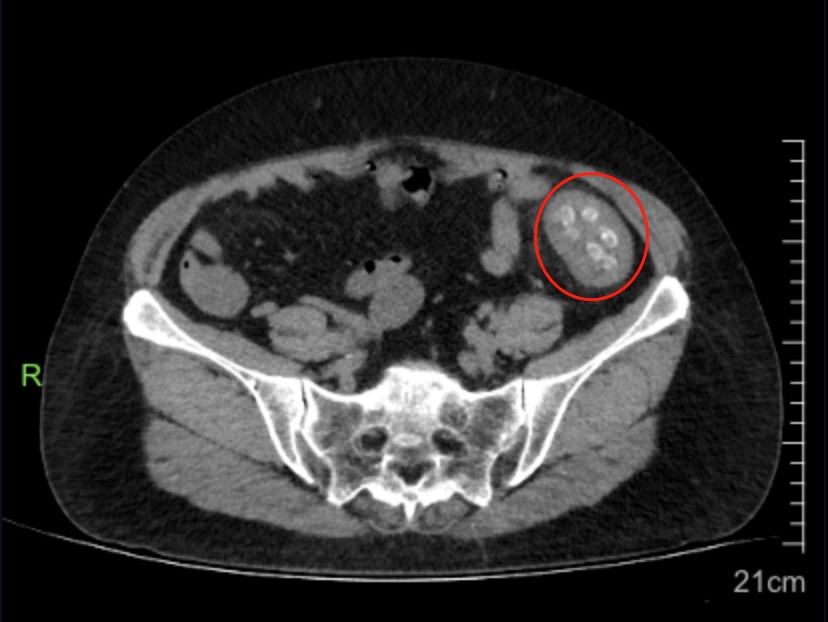

近期,浙江绍兴市人民医院肛肠科李振军博士在门诊遇到了一位王阿姨,因为肚子胀,大便几天没解,由儿子陪同来肛肠科就诊,李博士让王阿姨完善了腹部CT检查,检查结果提示:降结肠处肠管扩张明显,里面可看到数十颗圆圆的阴影,肠壁也有增厚表现。

图/腹部CT:红圈处即考虑是杨梅核

由于最近杨梅逐渐上市,坊间一直有吃杨梅核可以清肠解毒的传闻,李博士便仔细询问王阿姨,最近是否吃了挺多杨梅,还把核吞下去了?王阿姨随即表示是吃了几颗,但往年也会把杨梅核吞下去,从没出现肚子痛的情况,今年怎么会这样……